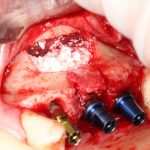

Я зафиксировал костный блок практически без адаптации на несколько винтов. Обрати внимание, что винты находятся в зоне, где не планируется установка имплантатов. Фиксация должна быть надежной, поскольку мне еще предстояла подготовка лунок для имплантатов. Трех винтов для этого вполне достаточно.

Дальнейшая адаптация костного блока свелась к сглаживанию острых краев. После чего я приступил к подготовке лунок и установке имплантатов.

Установка имплантатов.

Напомню, что для этой работы я выбрал субкрестальные имплантаты Ankylos C/X. Они прекрасно сочетаются с любым методом остеопластики.

Я не планирую установку супраструктур или коронок, поэтому на уровень первичной стабильности можно положить болт. Даже наоборот — чем меньше крутящий момент при установке, тем лучше. Для имплантатов Ankylos и подобных им, это особенно важно. В общем, момент силы при установке — не более 10-15 Нсм.

Ремарка: имплантаты с предустановленными имплантодержателями хороши тем, что с ними легко контролировать позиционирование имплантатов. В случае с Ankylos С/Х - еще и крутящий момент. Имплантодержатель должен отсоединяться от имплантата с легким щелчком. Если его клинит, и тебе приходится прикладывать для этого усилия, то ты, однозначно, превысил момент силы во время установки имплантата. Следовательно, жди проблем.

Глянем на то, что получилось:

Осталось адаптировать костный блок (убрать острые края), проверить его фиксацию и, при необходимости, добавить винты. Десятисекундное дело.